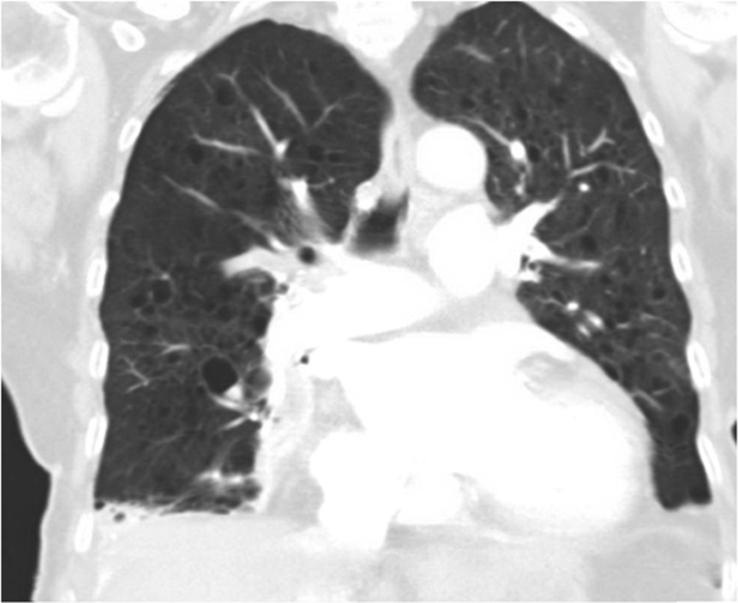

Transudative chylothorax is a rare type of pleural effusion. It has been described to be present in the setting of liver cirrhosis, heart failure, amyloidosis, nephrotic syndrome, superior vena cava thrombosis, sclerosing mesenteritis and heart failure. We present the case of an 86-year-old woman with a right-side transudative chylothorax associated with heart failure and lymphangioleiomyomatosis.

漏出性乳糜胸是一种罕见的胸腔积液类型。据描述,它可出现在肝硬化、心力衰竭、淀粉样变性、肾病综合征、上腔静脉血栓形成、硬化性肠系膜炎和心力衰竭等情况下。我们报告一例86岁女性患者,其右侧漏出性乳糜胸与心力衰竭及淋巴管平滑肌瘤病相关。